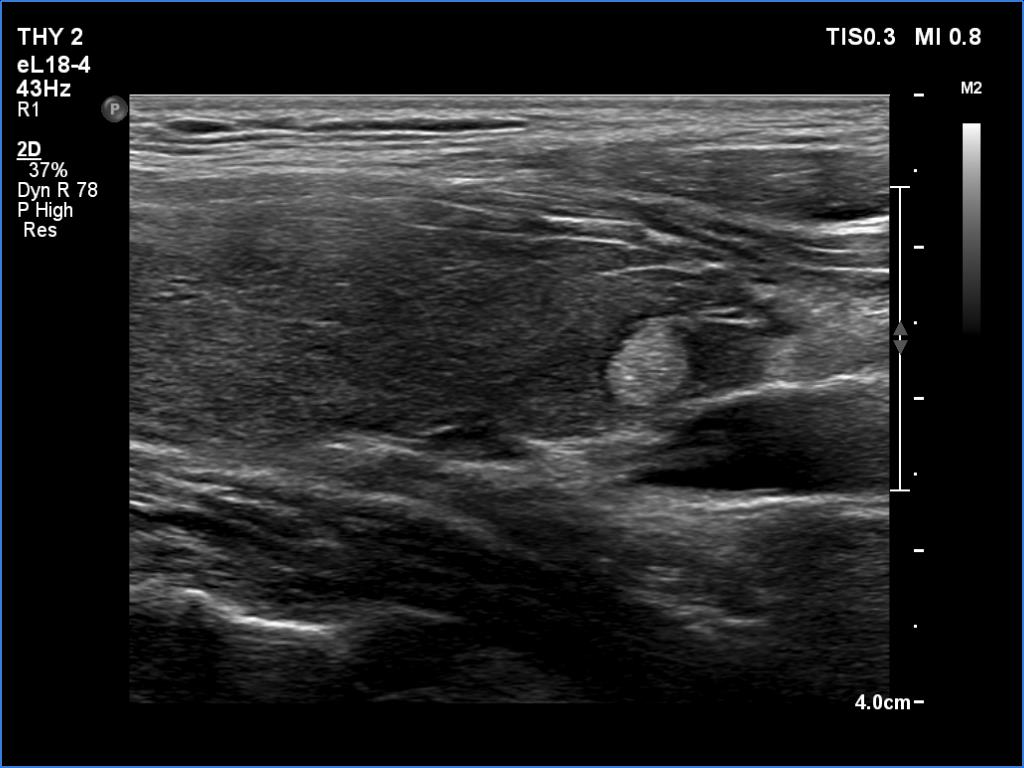

Follow-up investigation 4 months after the initial one (ultrasonographic picture 3)

Right lobe, longitudinal scan

Lower part of the right lobe. The discrete lesion reamined unchanged.